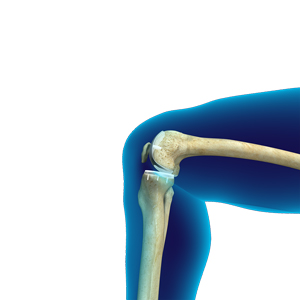

Unicondylar knee Replacement

Unicondylar Knee Replacement Surgeon in Palm Beach Gardens & Wellington Unicondylar knee replacement is a minimally invasive surgery in which only the …